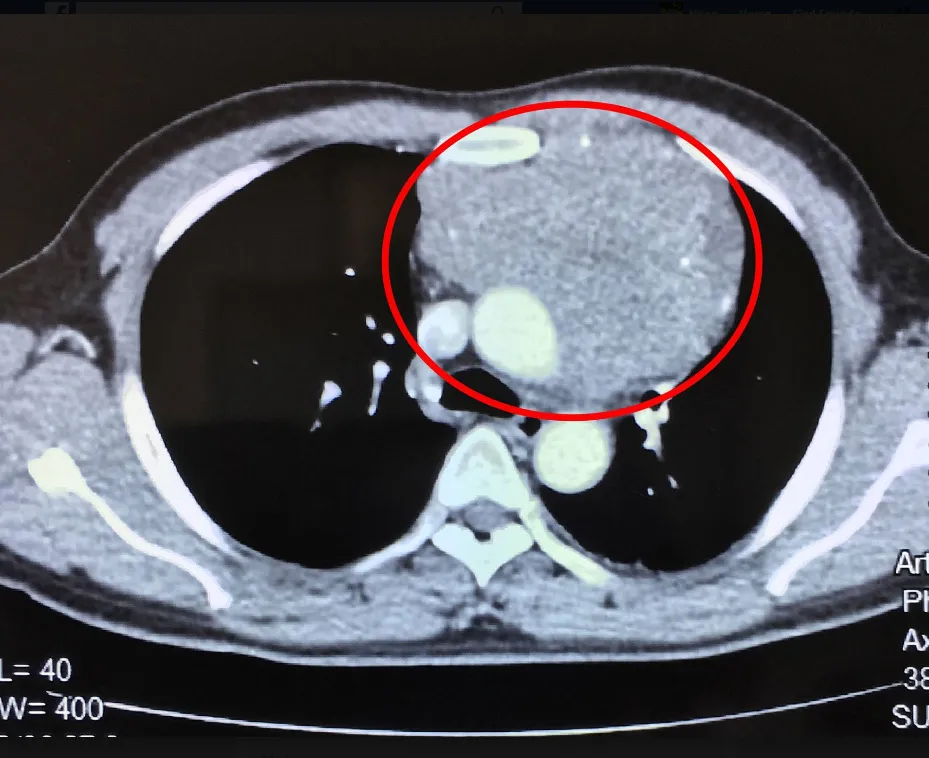

Hình chụp cắt lớp vi tính (CT) 160 lát cho thấy khối u nằm trong lồng ngực. Ảnh: CTV

Trước đó anh Q ho khan dai dẳng, tức ngực, khó thở liên tục nên đến khám tại BV Đa khoa Xuyên Á. Kết quả chụp cắt lớp vi tính (CT) có dựng hình 3D cùng các thăm dò cận lâm sàng cần thiết cho thấy một khối u rất to (13x15x18 cm) xuất phát từ trung thất trước xâm lấn rộng vào màng ngoài tim và lan ra sau dính vào động mạch chủ ngực xuống. Anh Q buộc phải lên bàn mổ.